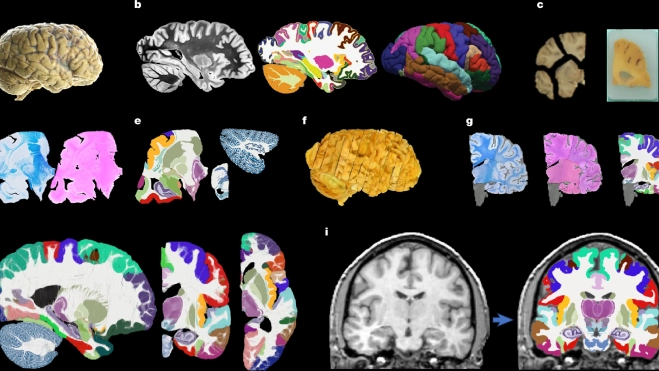

Un estudio desarrolla el mapa más completo y detallado del cerebro humano hecho hasta ahora, gracias a la inteligencia artificial. El atlas, llamado NextBrain, se ha publicado en la revista Nature y representa un paso adelante clave para entender y diagnosticar enfermedades neurológicas como el Alzheimer. El investigador Adrià Casamitjana, del grupo de investigación VICOROB de la Universitat de Girona (UdG) es el primer autor, fruto de su estancia postdoctoral en el University College London (UCL), donde ha colaborado con expertos internacionales en neuroimagen e ingeniería biomédica.

El atlas NextBrain, que ha sido desarrollado gracias a la ayuda de técnicas avanzadas de inteligencia artificial, es capaz de visualizar el cerebro humano in vivo a partir de resonancias magnéticas (RM) con una precisión sin precedentes.

El atlas NextBrain es el resultado de seis años de trabajo con muestras de tejido cerebral post mortem de cinco cerebros humanos. Cada cerebro fue diseccionado en más de 10.000 secciones microscópicas, teñidas, fotografiadas y reconstruidas digitalmente para crear un modelo 3D. La inteligencia artificial permitió alinear estas imágenes con escáneres MRI previos, corrigiendo distorsiones y otros artefactos provenientes de la disección, asegurando así una reconstrucción precisa.

A partir de este proceso, los investigadores identificaron y etiquetaron 333 regiones cerebrales, un trabajo que sin IA habría requerido décadas. El resultado es un atlas probabilístico representativo de la estructura cerebral adulta, aplicable tanto a cerebros vivos como a muestras post mortem.